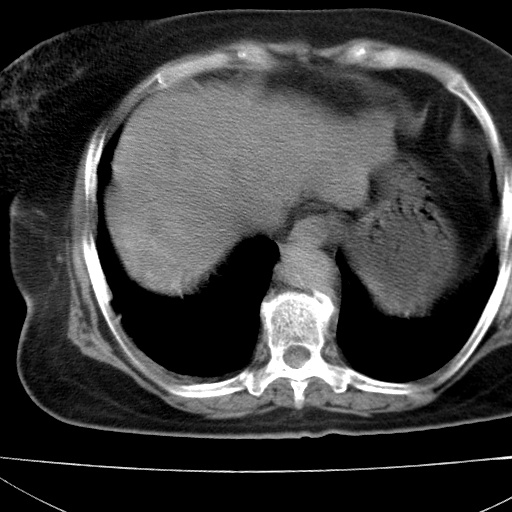

患者女74岁;右上腹胀痛1月,伴恶心,无发热;生活在疫水区。有术后病理及术后半年的追踪ct.

1)慢性血吸虫病(典型)。2)肝硬化。3)肝癌?4)胆囊炎。5)少量腹水。6)右侧少量胸腔积液。

肝脏体积缩小,肝裂增宽,边缘不平呈波浪状,肝右叶见分隔状条索形钙化,亦见多结节低密度灶,边界不清,肝周可见少许液性暗区,胆囊增大内密度均匀,脾脏下缘低于脏脏的下缘,胸腔亦见液性暗区,余未见明显异常.

诊断:1肝硬化并慢性吸血虫病,脾肿大

2肝内占位,考虑肝癌可能性大,建议做增强

3胆囊炎, 4少量腹水及胸水

胆囊增大饱满,壁增厚。胆囊颈部见软组织密度影。临近肝右叶前段见片状低密度区,病灶下部见条状钙化,少量胸腹腔积液。意见:胆囊颈癌累及肝脏。

病人以胆囊癌手术的,病理结果为中分化腺癌。

现在看看肝右叶内圆形低密度影你们考虑什么呢?

肝内圆形低密度影考虑扩张的胆管

请看3mm重建像如下: